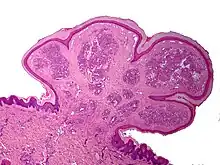

Un botriomycome (parfois écrit botryomycome) et aussi appelé granulome pyogénique ou hémangiome capillaire lobulé est une petite tumeur vasculaire inflammatoire bourgeonnante, saignant facilement, de couleur rouge vif, qui apparaît à la suite d'une petite plaie, souvent sur les doigts ou sur la main, en particulier lorsque celle-ci a subi un choc. Il peut aussi apparaître au bord d'un ongle incarné, notamment s'il y a eu frottement et irritation dans une chaussure trop étroite.

C'est un petit « bourgeon charnu » très vascularisé, ultra-sensible, mou et bénin provoqué par la cicatrisation de la plaie qui ne s'arrête pas. Il saigne facilement et sécrète régulièrement de la lymphe.

L'installation et la croissance rapide, ainsi qu'un traumatisme initial, permettent souvent d'affirmer le diagnostic. Toutefois l'examen histopathologique est toujours nécessaire.